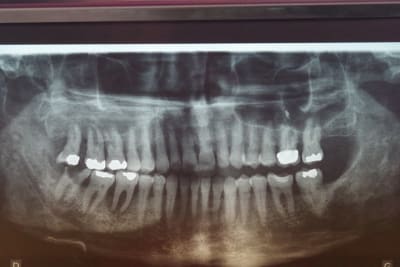

Sur la pano, on voit bien le condyle gauche. Il n'est pas en dehors de la cavité glénoide. Il n'y a pas de luxation de l'ATM gauche. Le problème est très probablement d'origine fonctionnelle (je dirai même que la bouche ne semble n'avoir jamais été fonctionnelle).

je serais plus de l'avis de sumble ( pas de luxation )

+ il n'y a pas de decalage du point inter-incisif

+ sur la pano la mand n'est pas decalée vers le bas

+ le haut est bien tordu

J'ai retrouvé une pano ( pas très nette: depuis la clinique radio s'est améliorée) d'il y a presque 2 ans et on voit deux choses:

1°) le problème occlusal existait mais sans doute moins prononcé. J'avoue m'être polarisé sur la paro et suis passé à côté du problème occlusal.

2°) Le condyle mandibulaire gauche me semble bien à sa place.

je ferai passer ces jours ci une pano bouche fermée centrée sur les condyles.